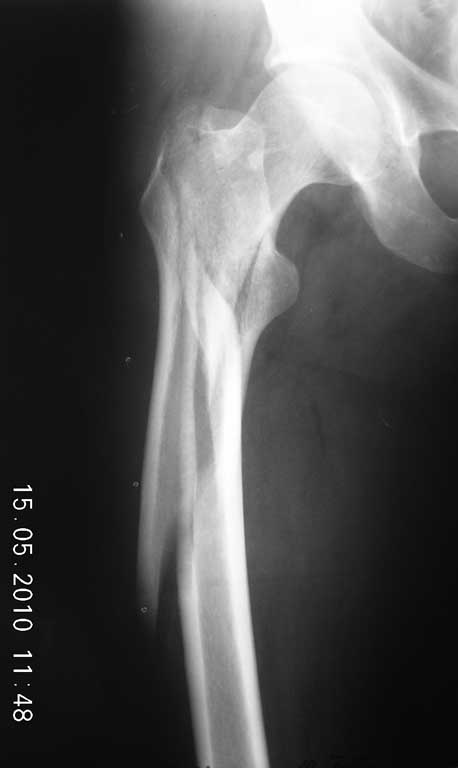

добавлю боковую проекцию(на месте) Какой стержень предназначен для таких переломов?

|